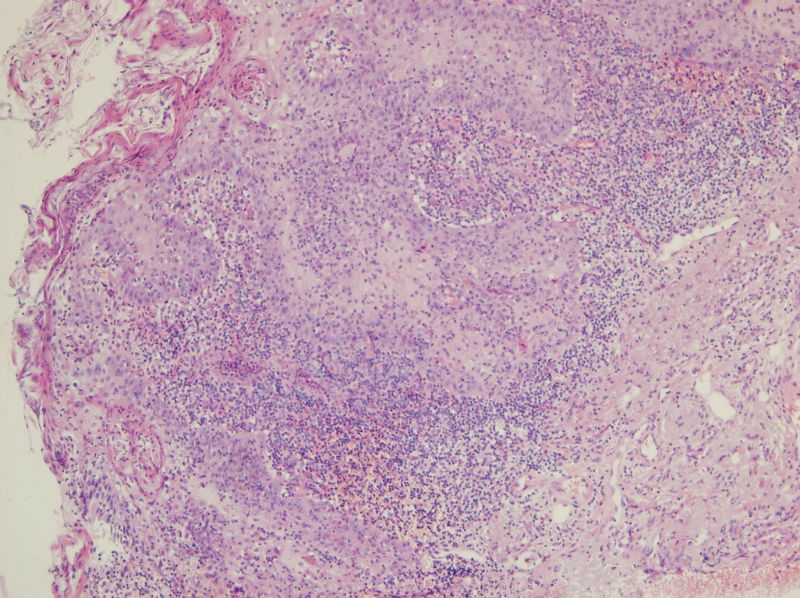

男,45岁,上唇菜花样肿物,请老师指教

图4